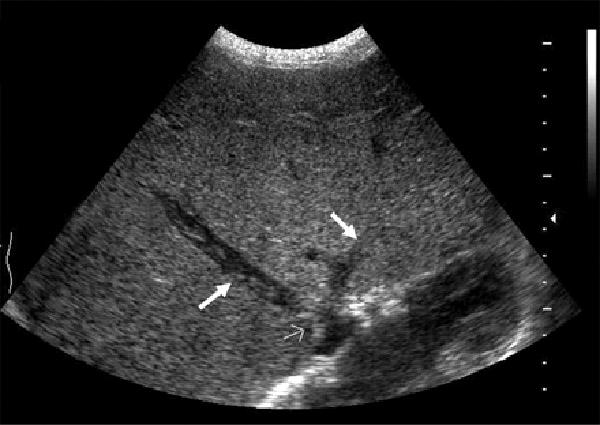

Mirizzi SYndrome

impacted stone in the cystic duct or GB neck

presence of two tubular structures representing the bile duct above the level of the cystic duct

Mirizzi SYndrome

impacted stone in the cystic duct or GB neck

presence of two tubular structures representing the bile duct above the level of the cystic duct